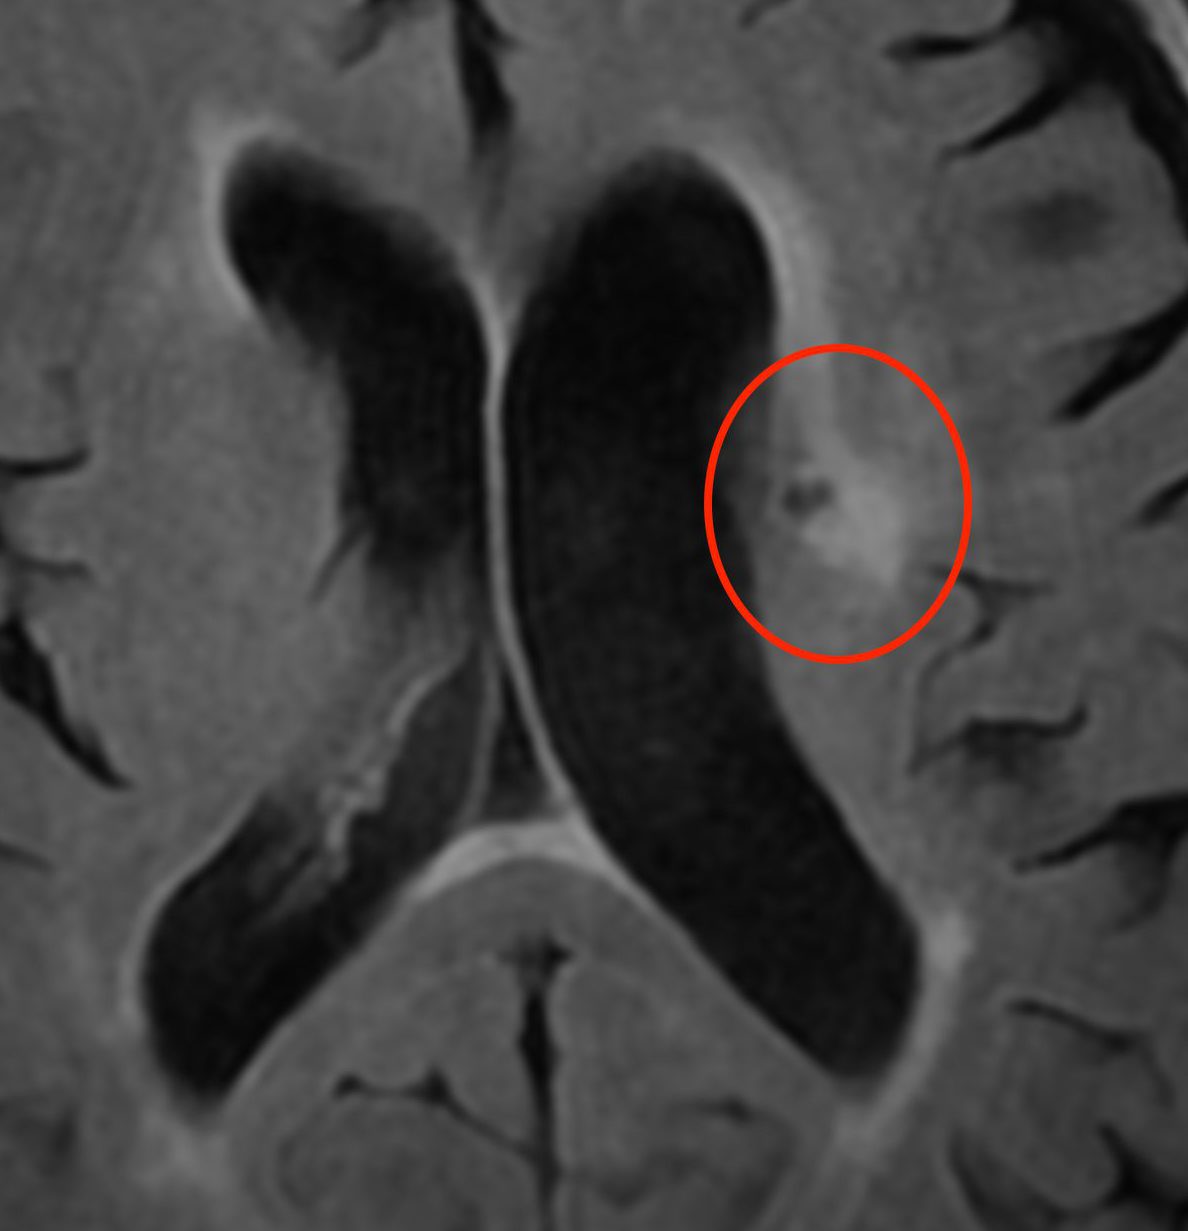

未破裂脳動脈瘤

動脈瘤があるだけでは無症状です。症状が出てからでは遅いので、大きい場合には手術を行います。